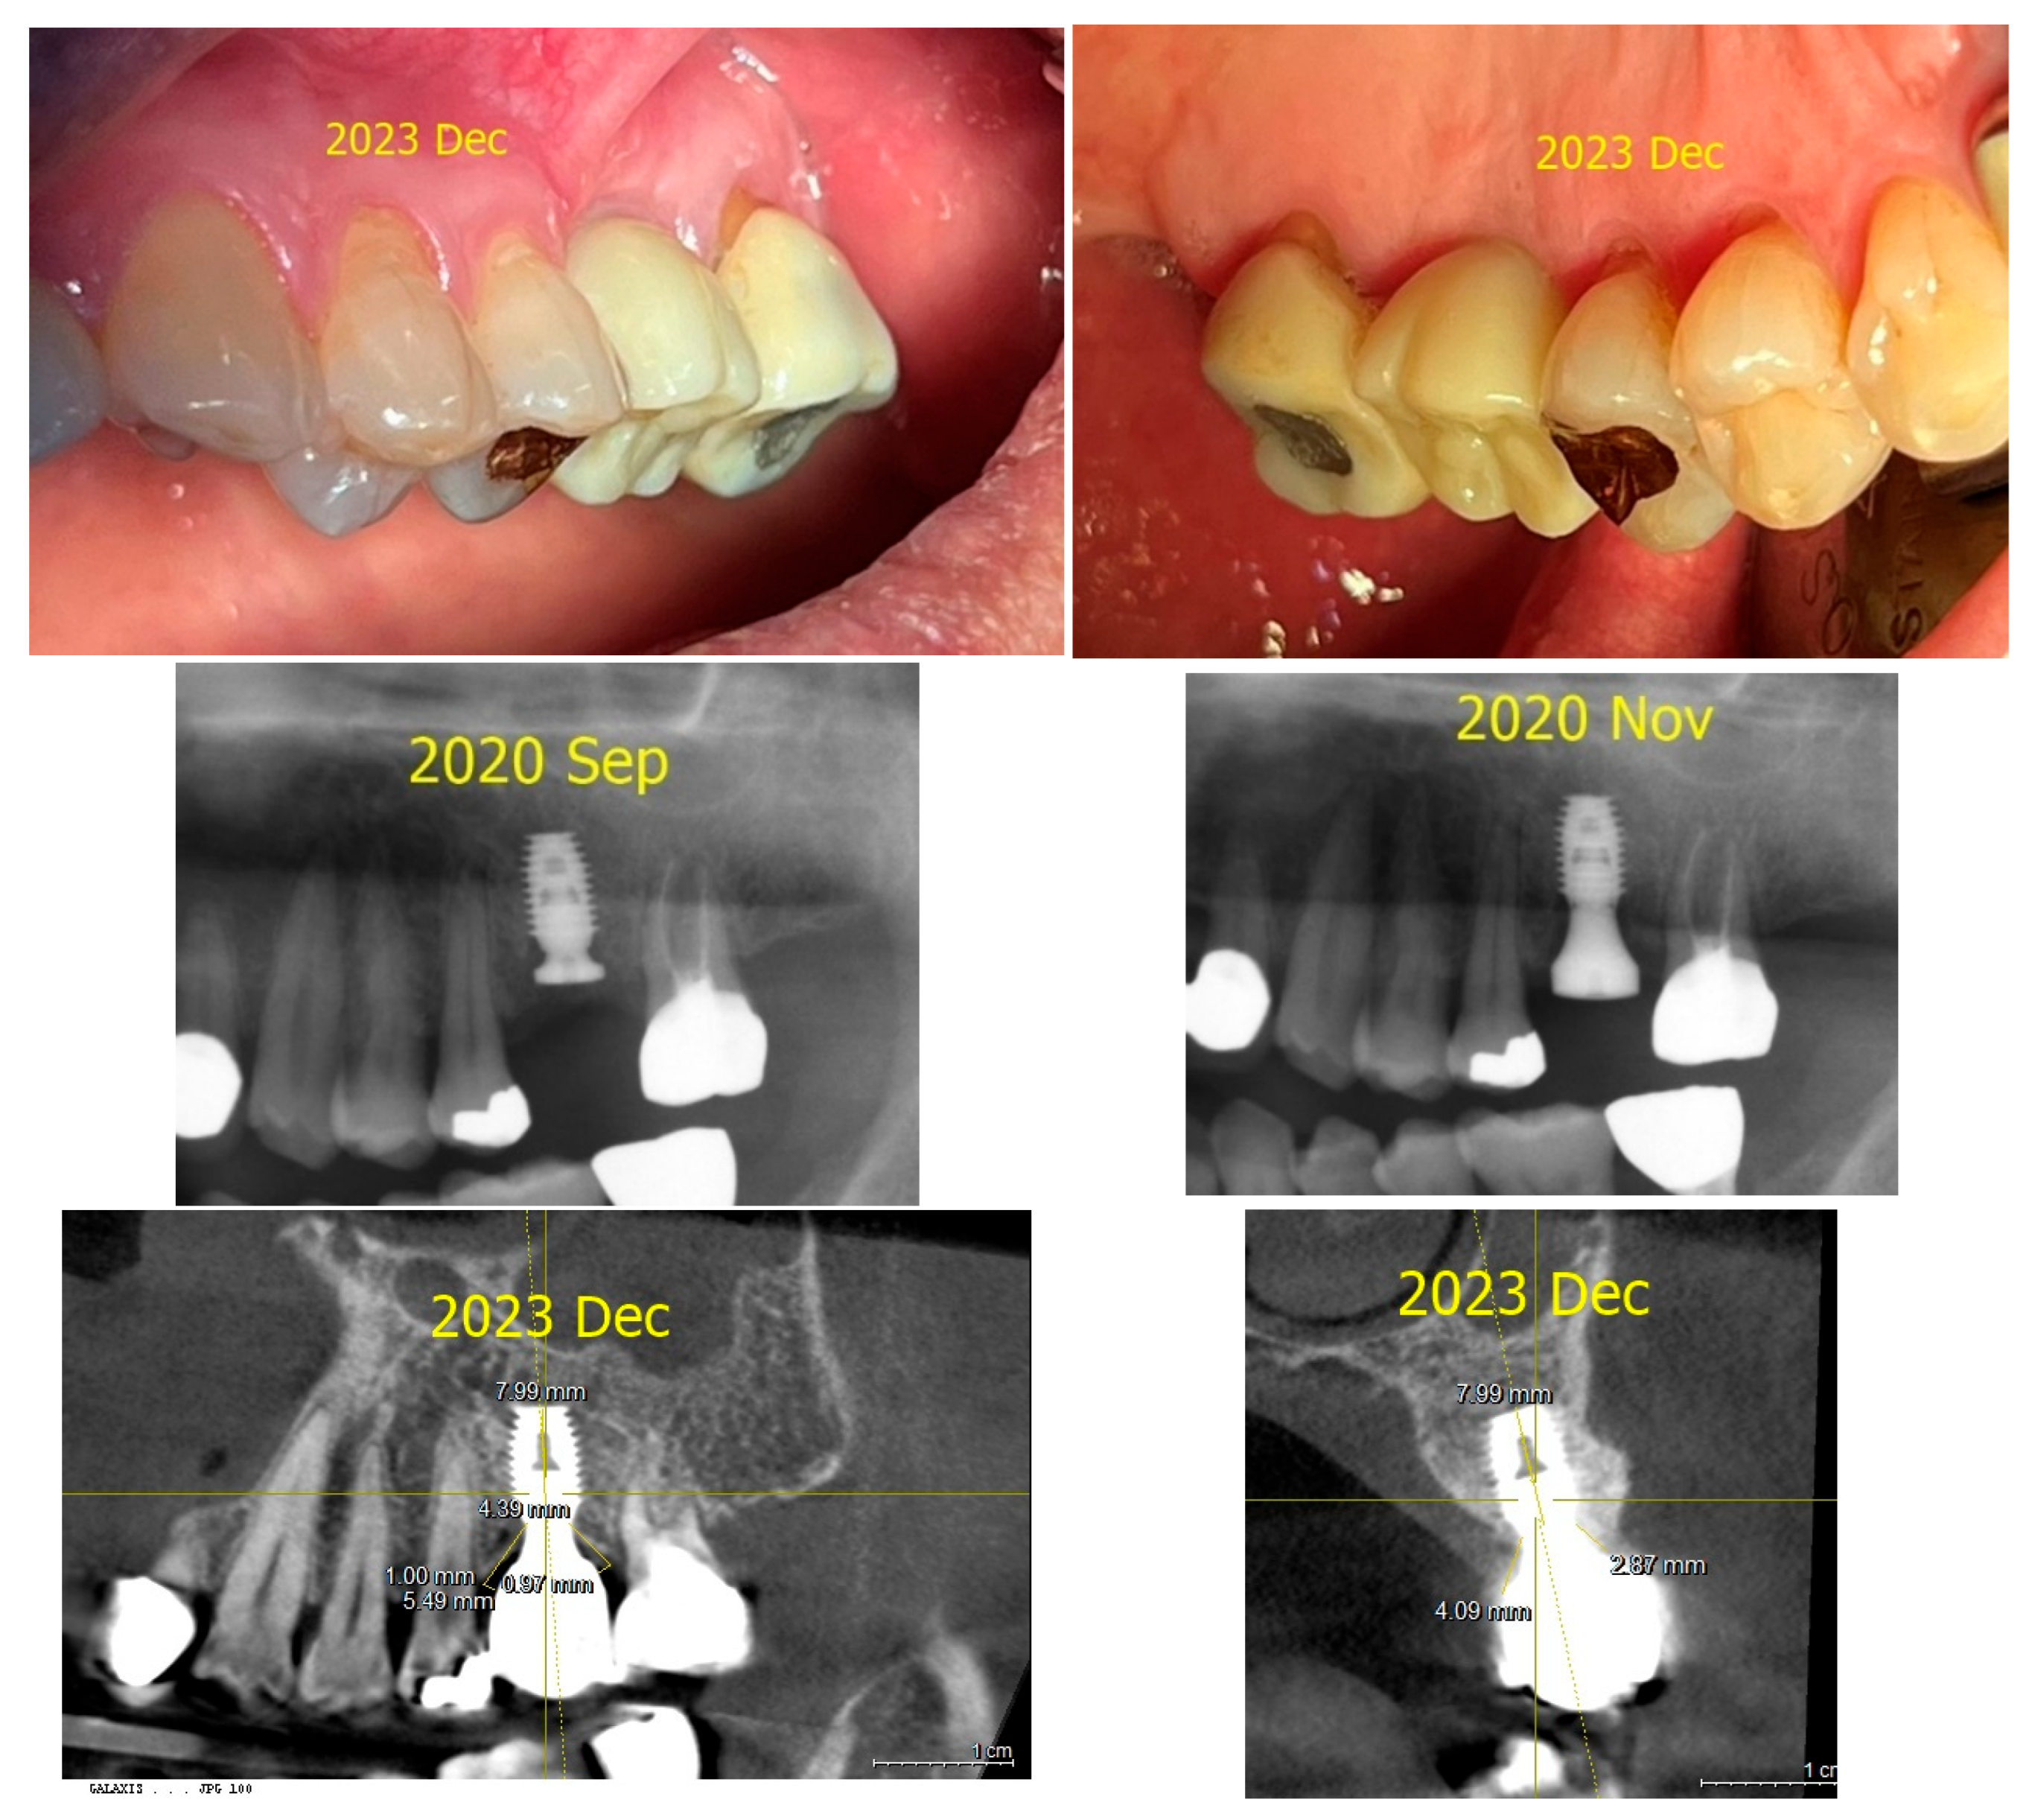

2. Case Presentation

3. Radiographic and Clinical Findings